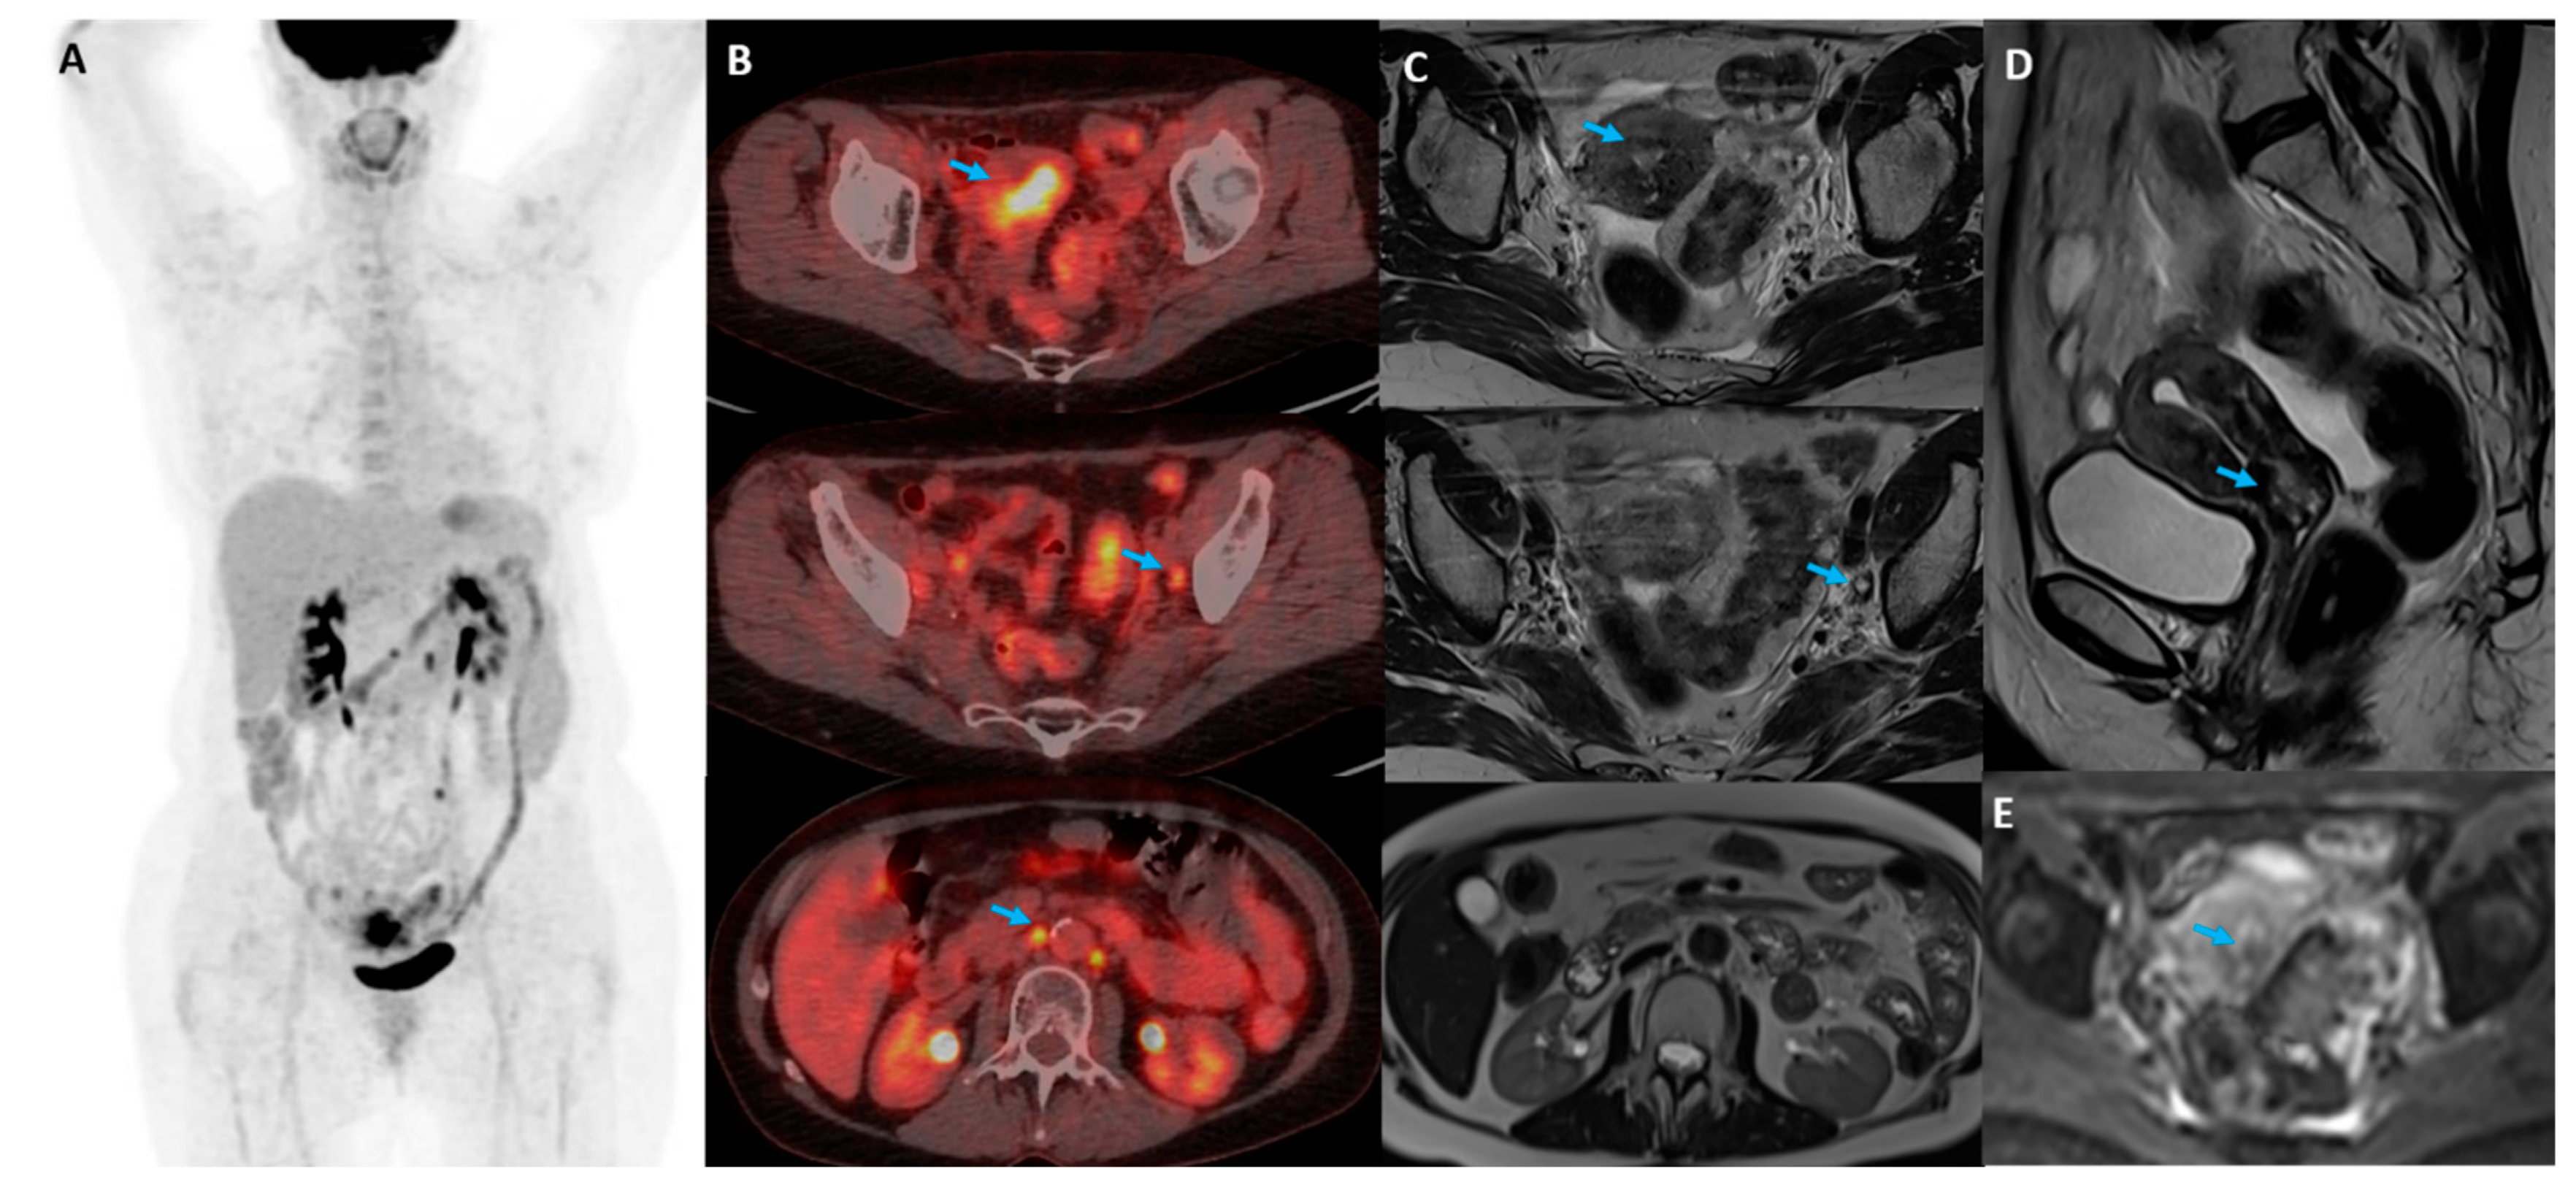

- Perrone, A.M.; Dondi, G.; Coe, M.; Ferioli, M.; Telo, S.; Galuppi, A.; De Crescenzo, E.; Tesei, M.; Castellucci, P.; Nanni, C. Predictive Role of MRI and 18F FDG PET Response to Concurrent Chemoradiation in T2b Cervical Cancer on Clinical Outcome: A Retrospective Single Center Study. Cancers 2020, 12, 659. [Google Scholar] [CrossRef]